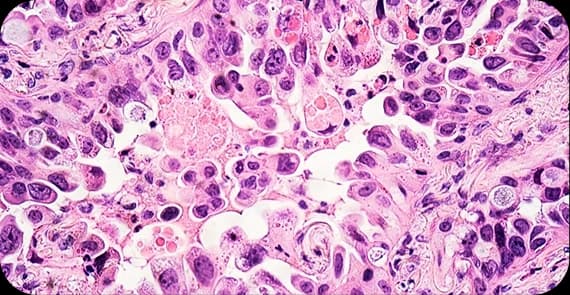

When patients ask what stomach cancer is, the explanation begins at the cellular level. Stomach cancer, also known as gastric cancer, occurs when cells in the stomach lining develop genetic mutations that cause uncontrolled growth.

Normally, stomach cells grow and regenerate in an organised manner. In stomach cancer, abnormal cells multiply and may form a tumour within the stomach wall. Over time, the cancer can invade deeper layers and spread to lymph nodes or distant organs.

There are different types of stomach cancer depending on the cells from which the tumour arises.

The most common type, originating in the glandular cells of the stomach lining.